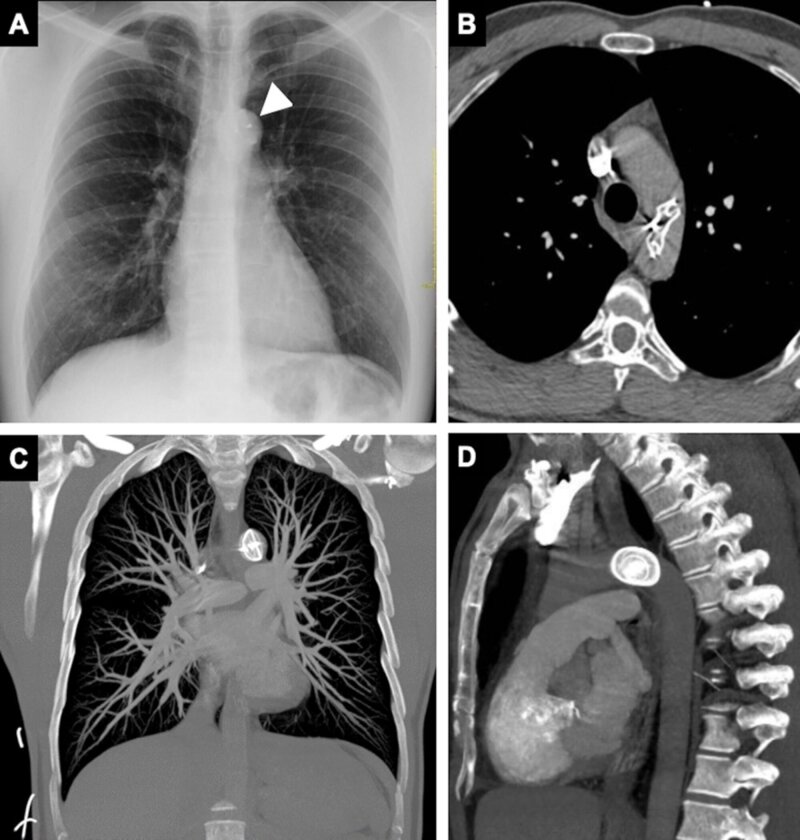

Atrial septal defect (ASD) is a common cardiac defect with significant implications if left untreated. Although open heart surgery is the traditional approach, transcatheter closure devices, such as the Amplatzer™ Septal Occluder Device, have gained prominence due to advantages like shorter hospital stays and reduced costs. Among potential complications, device migration is a rare complication, with an incidence of 0.5 to 1.1%. We report a rare case of migration of an Amplatzer™ device in an asymptomatic patient, diagnosed 6 months after its implantation. After detecting the issue, the medical team opted for percutaneous device removal followed by open surgery to correct the ASD. In conclusion, managing Amplatzer™ device embolization requires careful consideration of the patient's circumstances and device anatomy. This case highlights the importance of correlating clinical and imaging findings when selecting the management approach and assessing the feasibility of a less invasive approach in cases of late migration.